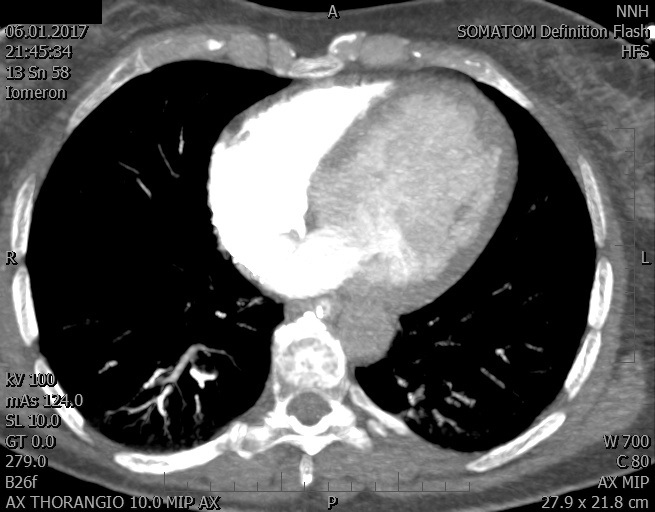

Video 1 - Akutní koronarografie prokázala normální nález na věnčitých tepnách s výjimkou suspekce na lehký spasmus na pravé koronární tepně.Echokardiograficky byla zjištěna těžká dysfunkce dilatované levé komory s nezvětšenou pravou komorou (video 2).

Video 2 - Echokardiograficky byla zjištěna těžká dysfunkce dilatační levé komory s nezvětšenou pravou komorou.Pro nejasnou příčinu zástavy jsme provedli i vyšetření výpočetní tomografií (CT), které vyloučilo plicní embolizaci (série 1 - soubory na konci článku). V den přijetí při přetrvávající oběhové nestabilitě byla nemocná opakovaně defibrilována pro fibrilaci komor se stabilizací rytmu po podání amiodaronu a mesocainu. Dle hemodynamických měření se jednalo o těžký kombinovaný šok. Vstupní laboratorní vyšetření bylo bez větších pozoruhodností. Posléze jsme doplnili anamnézu od příbuzných a zjistili, že pacientka užila do dvou hodin před srdeční zástavou první tabletu amoxicilinu na lehký respirační infekt. Při nevýtěžnosti vstupních vyšetření a nových anamnestických informacích jsme doplnili 14 hodin po kolapsu vyšetření koncentrace tryptázy v séru, která byla extrémně zvýšena (tabulka 2), což nás vedlo k podezření na anafylaxi.